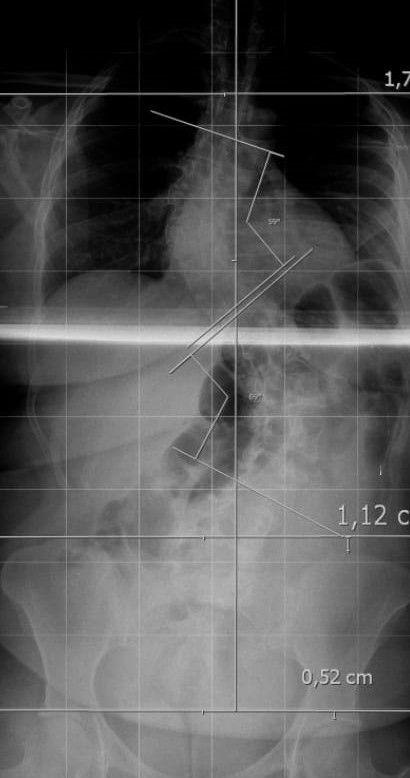

“La escoliosis severa se visualiza a través de radiografías completas de la columna.

Cuando la curvatura supera los 40 grados, evaluamos la intervención quirúrgica”, detalló Reble.

La nueva técnica implica un paso previo crucial: una tomografía del paciente que se carga al sistema de navegación. Este software guía al equipo quirúrgico sobre qué tipo de tornillos utilizar y cómo colocarlos con precisión milimétrica.